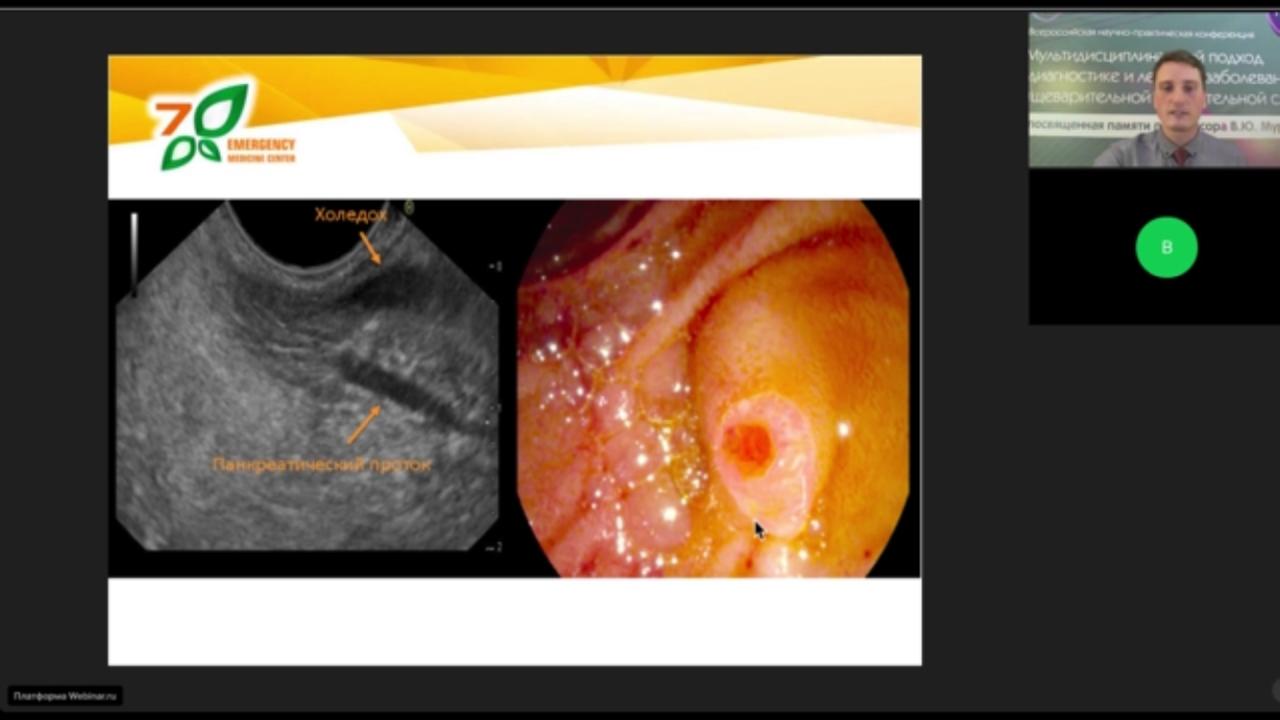

Своим опытом лечения поделился и врач -эндоскопист Городской клинической больницы N7 Казани Денис Валерьевич Макаров. Тема выступления «Комбинирование ЭУС+ЭРХПГ в рутинной практике. Клинический опыт» вызвала активное обсуждение у собравшихся коллег.